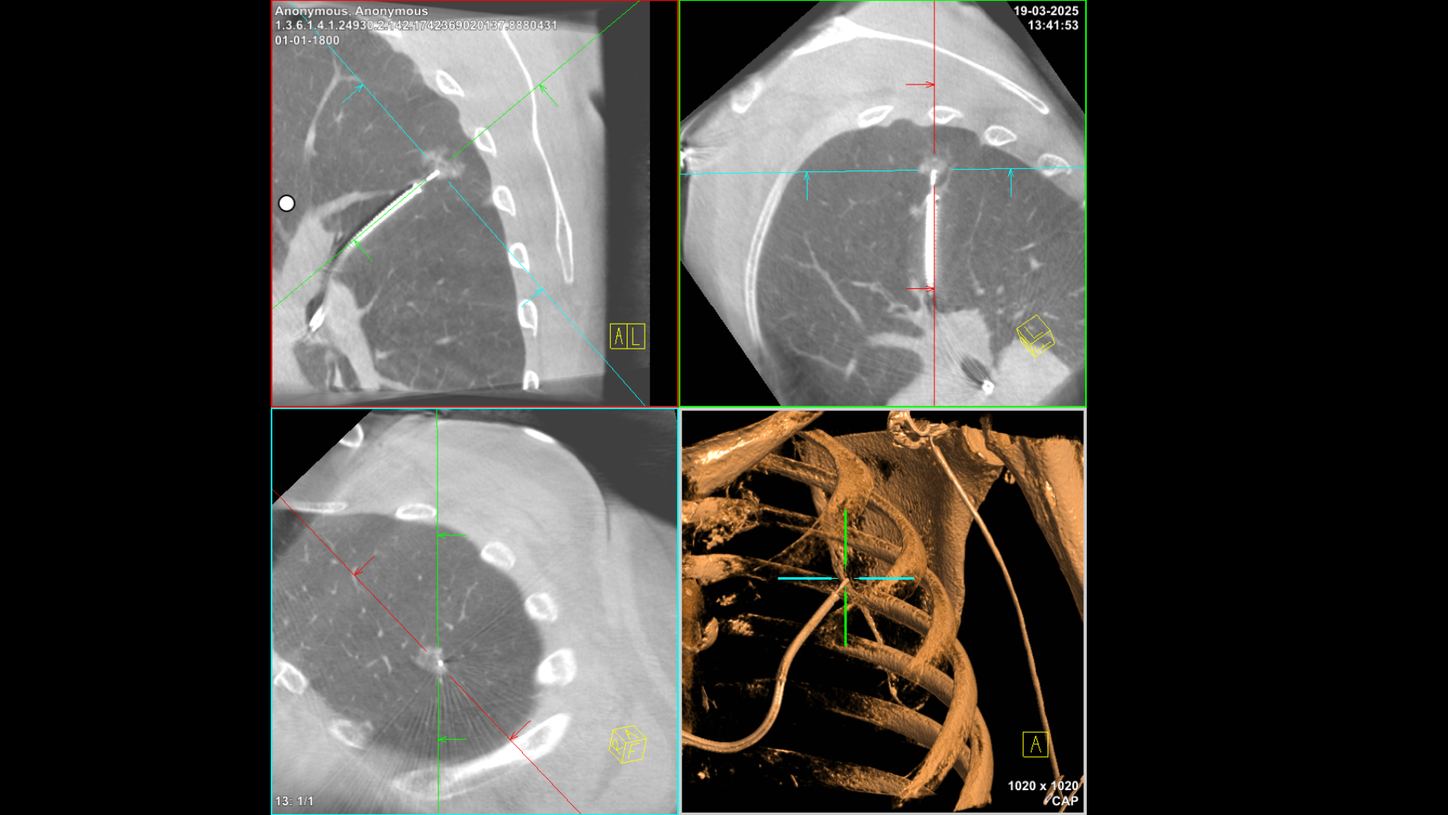

Combining cone beam CT with robotic-assisted bronchoscopy has several additional advantages, as Gaisl explains: 鈥淔irst, complexity goes down for everyone. This means we can do more procedures a day. The procedure time for robotic-assisted bronchoscopy with cone beam CT is 37 minutes. This is similar to the 34 minutes needed for conventional bronchoscopy with 2D fluoroscopy [2]. Second, the radiation dose for each patient goes down. Third, we鈥檙e also able to see where we are in the lesion. Sometimes the integration is so helpful that we no longer need a second 3D spin. At USZ, the average is 1.25 spins per lesion [2].鈥